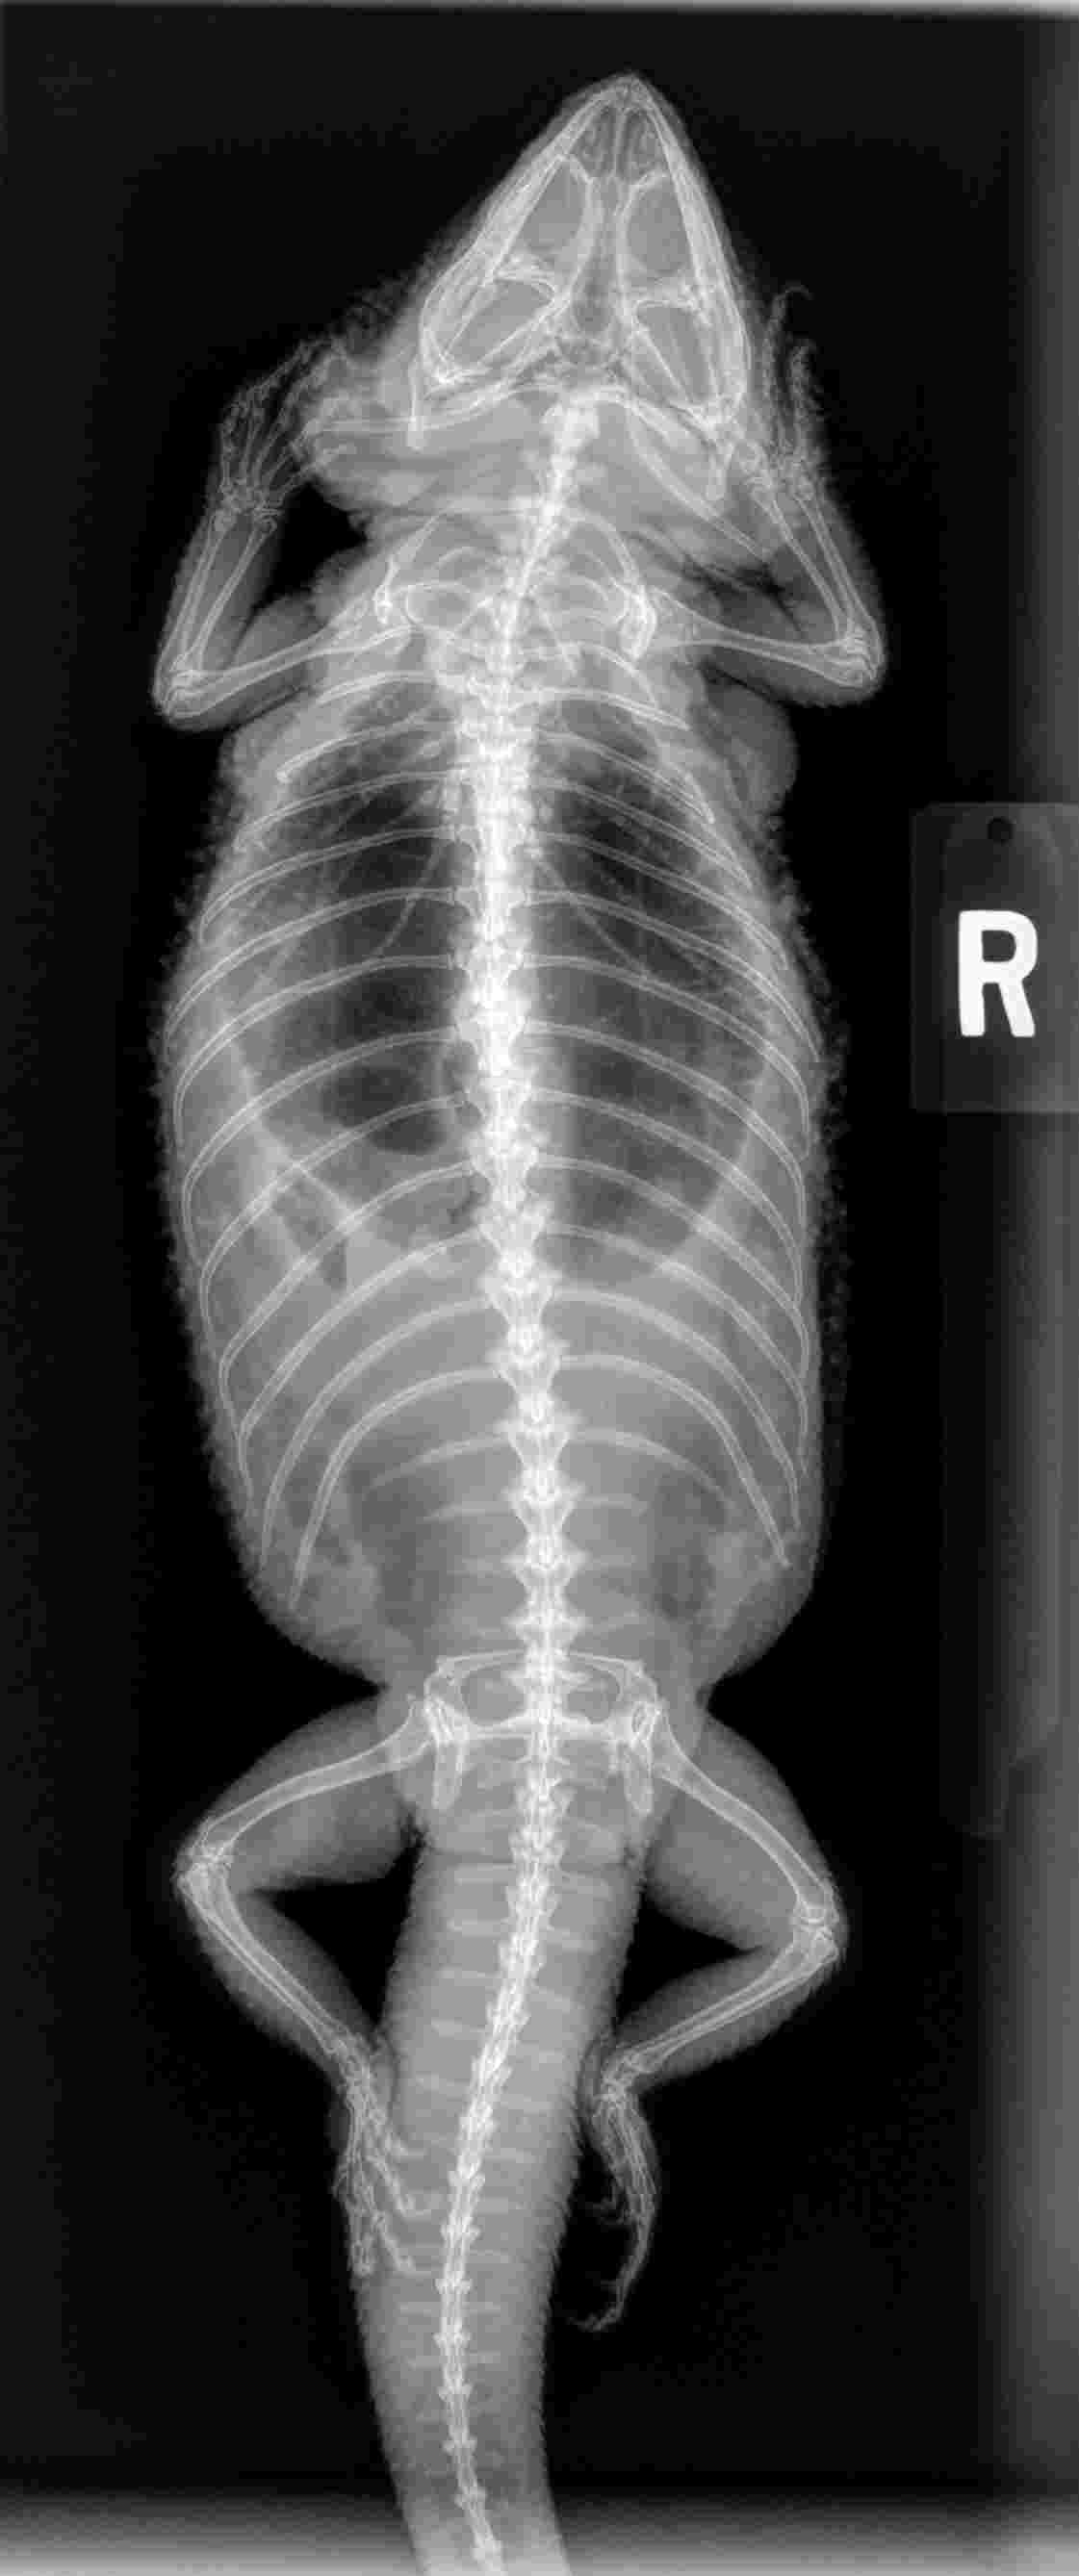

Pet's info: Reptile | Bearded Dragon | Female | unspayed | 7 years old | 1.2 lbs

My bearded dragon is anemic, high uric acid and glucose. She has low blood count. Is there anything I can do for her? Any foods, probiotics, antibiotics, fluids, or treatment that can be done to help her? Please help and thanks so much. She is my best friend and I don't want to lose her.

Thanks for reaching out about Trudy and including images. The blood work does not indicate kidney problems as uric acid and potassium are not elevated. Severely anemic. A transfusion is recommended but you still need to determine where to blood loss is from, possible gastrointestinal. Endoscopy, parasite exam, intestinal/fecal cultures might be needed. Trudy should be hospitalized. Good luck.